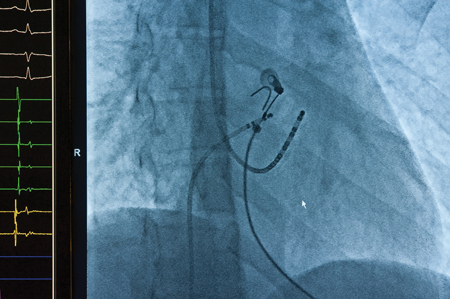

CHICAGO, IL – Marker bands are small metal bands attached to catheters for minimally invasive medical procedures. The bands are radio-opaque (highly visible under x-ray), giving physicians much-needed visibility of the catheter location during procedures (FIGURE).